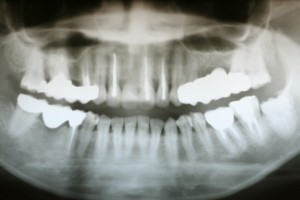

レントゲン写真で歯肉の下に虫歯が見られます。